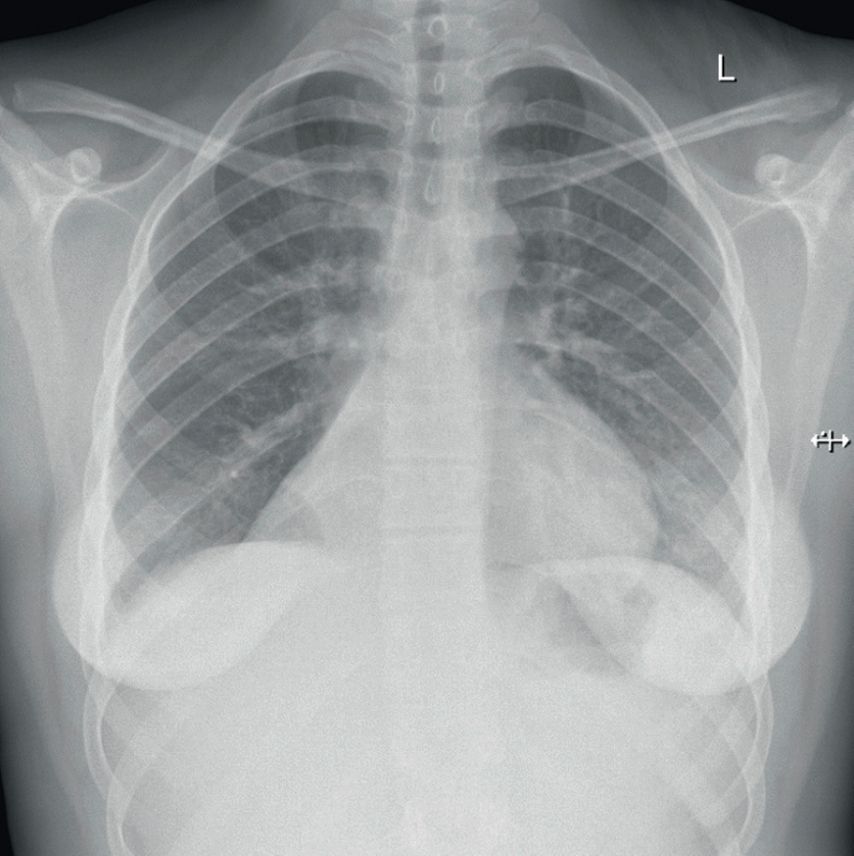

In der daraufhin angefertigten Röntgen-Thoraxaufnahme zeigten sich Zeichen einer zentralen Pneumonie sowie der Verdacht auf eine Komplettatelektase des rechten Unterlappens (Abb.1).

Zwei Jahre zuvor war die Patientin mit der gleichen Symptomatik in einer anderen Kinderklinik aufgenommen worden. Auch hier hatte sich in der radiologischen Diagnostik eine Atelektase im Bereich des rechten Unterlappens gezeigt. Die empfohlene weiterführende Diagnostik zur Abklärung des Befundes wurde damals nicht wahrgenommen.